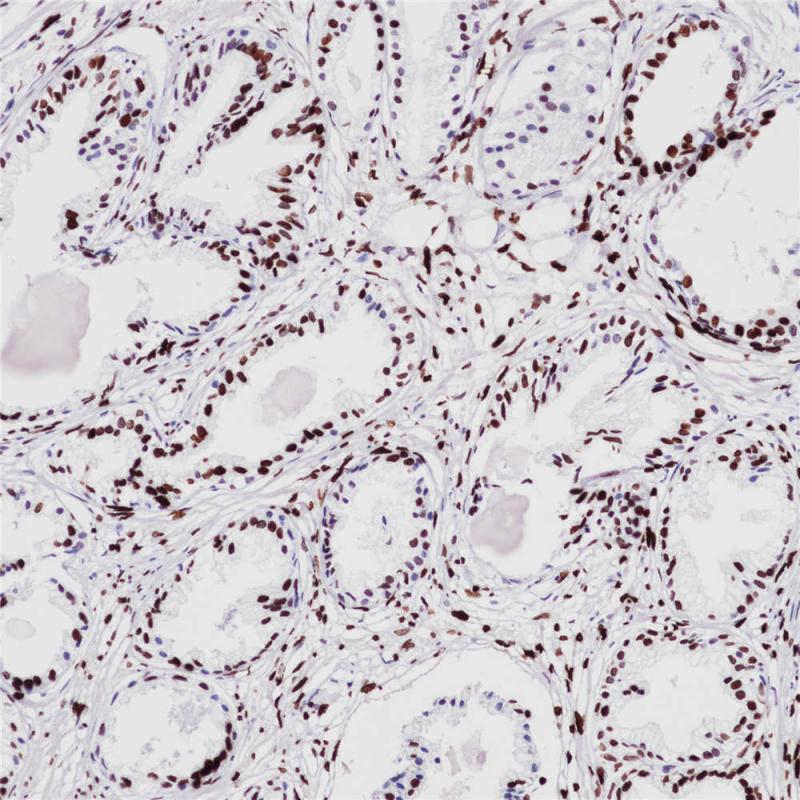

Phosphohistone H3 (PHH3) 重组兔单克隆抗体

磷酸化组蛋白H3(PHH3)是一种核心组蛋白,它和其他组蛋白构成了真核细胞染色质的主要蛋白组分。在哺乳动物细胞中,PHH3在间期表达量可以忽略,但在有丝分裂的染色质凝聚时达到最高值。免疫组化研究显示,PHH3抗体可特异性检测处于第10、28位丝氨酸磷酸化时的核心组蛋白H3。因此,PHH3可作为有丝分裂特异性标记物,鉴别细胞凋亡体、核分裂碎片,对于中枢神经系统肿瘤、黑色素瘤、软组织肿瘤、GIST等,有助于肿瘤病理分级,预后判断等。